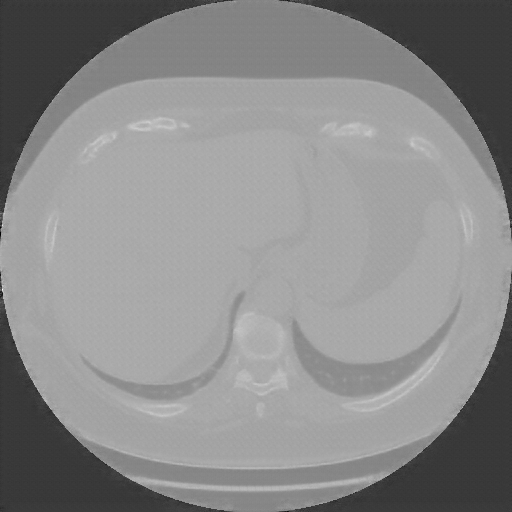

Reconstructed NATIVE CT scan (cycle consistency)

No window - Raw intensity values

Lung window (WL -600, WW 1500 β†’ Low βˆ’1350, High +150)

Mediastinum window (WL 40, WW 400 β†’ Low βˆ’160, High +240)